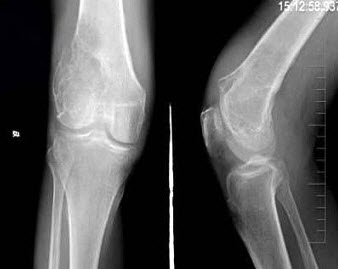

男,30岁,右膝关节酸胀,疼痛不适5个月,X线检查如图所示,最可能的诊断是( )

A:骨巨细胞瘤

B:骨囊肿

C:骨血管瘤

D:动脉瘤样骨囊肿

E:以上均不正确